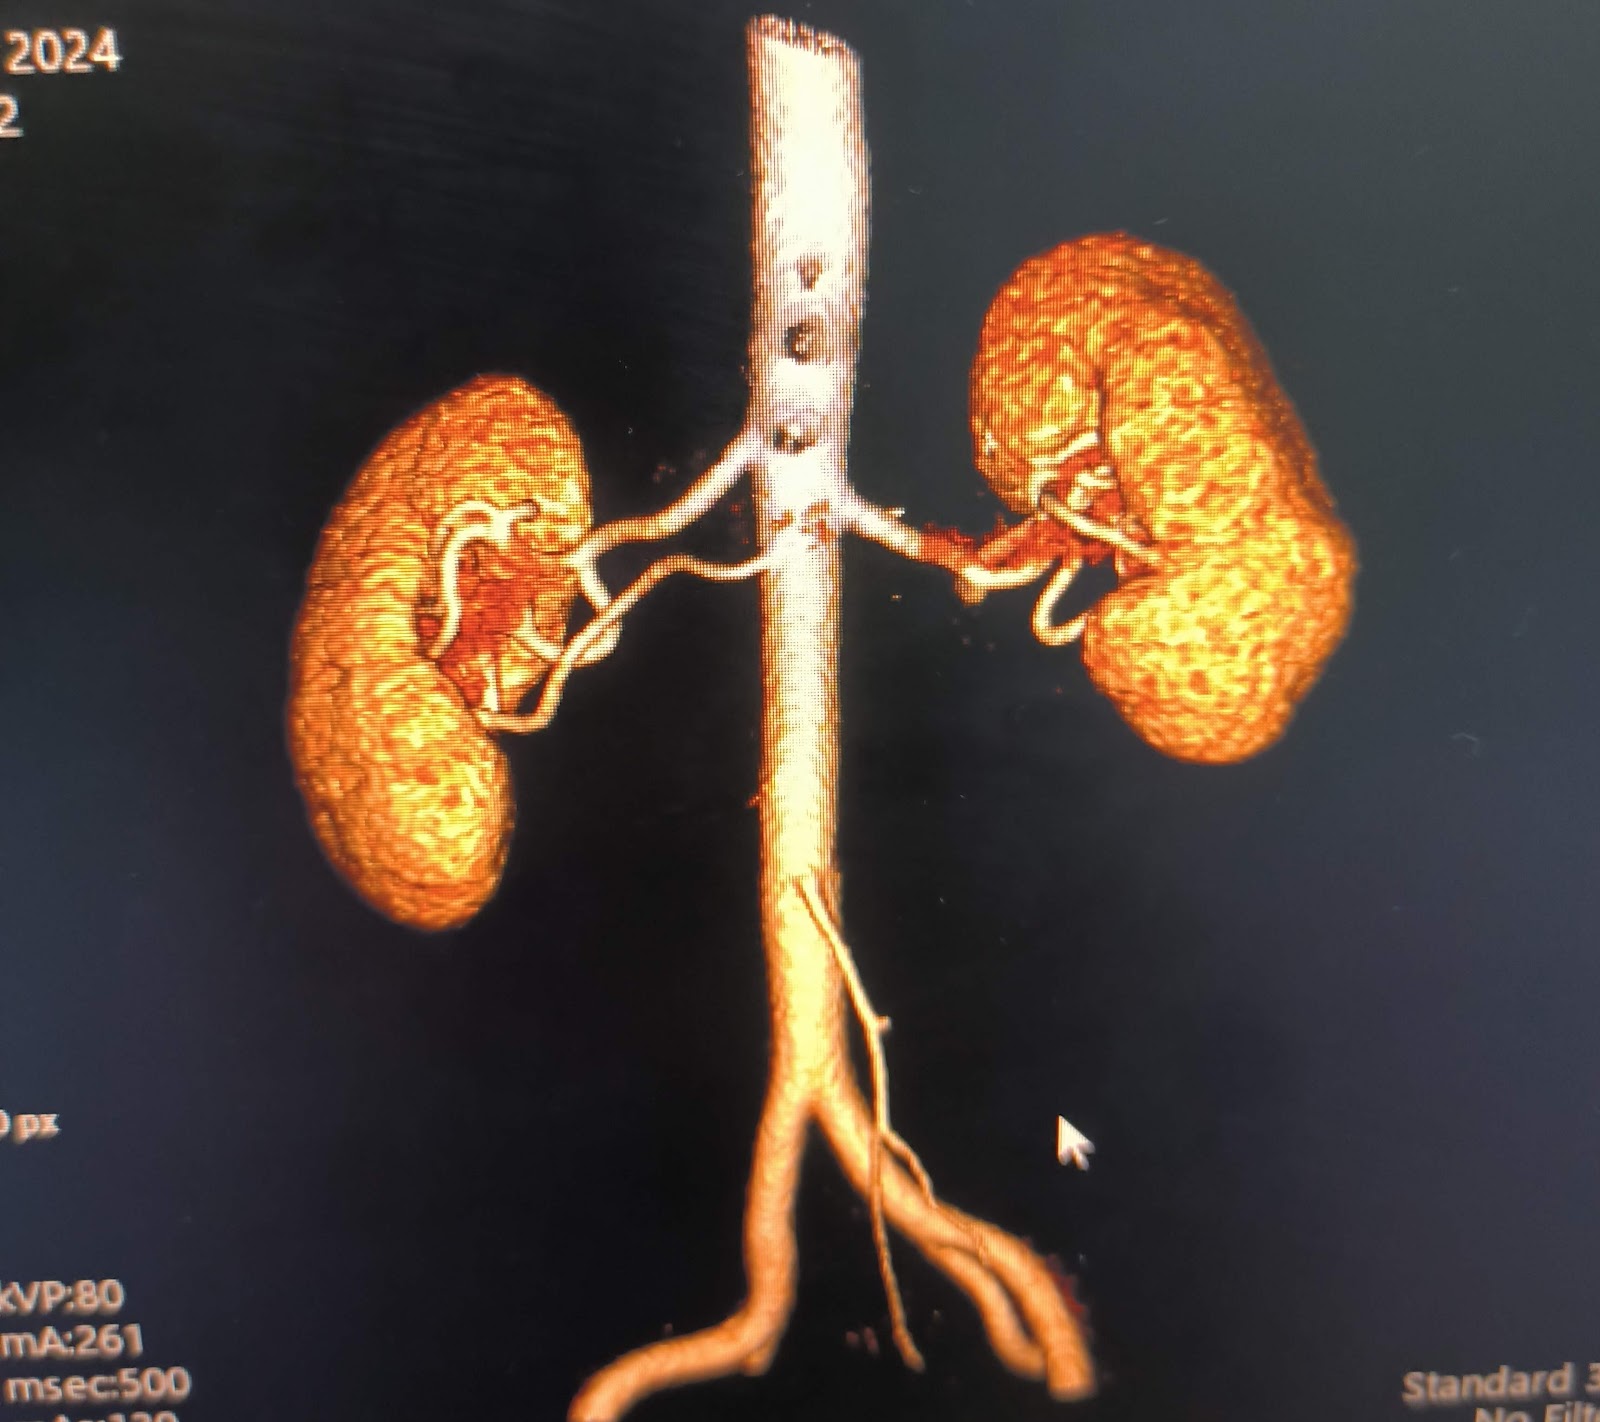

El Dr. Ulises Mejía es un urólogo destacado en Colima, reconocido por su profesionalismo y atención personalizada. Ubicado en Av. Constitución 2080, Puerta del Sol, ofrece servicios especializados en salud urológica para pacientes que buscan un cuidado integral y de calidad. Con una calificación de 5 estrellas basada en 10 opiniones, sus pacientes destacan su capacidad, inteligencia y dedicación en cada consulta y procedimiento. El Dr. Mejía se caracteriza por brindar un trato cercano y atento, asegurando que cada paciente reciba un diagnóstico preciso y un tratamiento efectivo. Sus servicios incluyen diagnóstico y manejo de enfermedades urológicas, cirugías y seguimiento postoperatorio, siempre con un enfoque humanizado. Para agendar una cita o solicitar información, puede contactarse al teléfono 312 114 8230 o visitar su perfil profesional en Instagram. Si busca un especialista confiable y con amplia experiencia en Colima, el Dr. Ulises Mejía es una opción recomendada para el cuidado de su salud urológica.

Dr. Ulises Mejía is a highly regarded urologist based in Colima, known for his professionalism and personalized care. Located at Av. Constitución 2080, Puerta del Sol, he provides specialized urological health services to patients seeking comprehensive and quality care. With a perfect 5-star rating from 10 reviews, patients highlight his expertise, intelligence, and dedication during every consultation and procedure. Dr. Mejía is recognized for his attentive and compassionate approach, ensuring accurate diagnoses and effective treatments. His services include diagnosis and management of urological conditions, surgeries, and postoperative follow-up, all delivered with a patient-centered focus. To schedule an appointment or request more information, contact him at 312 114 8230 or visit his professional Instagram profile. For those looking for a reliable and experienced urologist in Colima, Dr. Ulises Mejía is a highly recommended choice for urological health care.